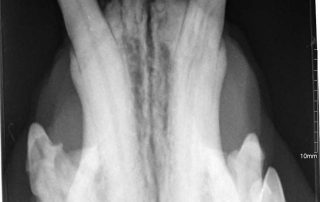

Werden die Zähne nicht täglich intensiv geputzt, bleibt ein Belag, die „Plaque“ zurück. In diese Schicht lagern sich nach und nach Mineralstoffe und Bakterien ein. So entsteht an den Außenflächen der Zähne harter, braungrauer Zahnstein. Durch die Eiter erregenden Keime in Plaque und Zahnstein entzündet sich das Zahnfleisch, es wird rot und riecht Übelkeit erregend. Schreitet die Zahnfleischentzündung (Gingivitis) weiter voran, verlieren die Zähne oft vollständig ihren Halt, bleiben aber als ständiger Entzündungsherd häufig noch jahrelang im Kiefer. Häufig entstehen, vielfach unterhalb des Zahnfleischsaumes, Löcher in den Zahnhälsen und Zahnwurzeln. Diese werden als FORL (feline odontoklastische resorptive Läsionen) bezeichnet; Die Zahnsubstanz löst sich regelrecht auf.

Zunächst ist die Entfernung des krank machenden Zahnsteins und die Wiederherstellung eines gesünderen Zahnfleisches wichtig. Da die Beläge auf den Zähnen mit einem Ultraschallgerät entfernt und die Zähne anschließend aufwändig poliert werden müssen, ist eine schonende altersangepasste Vollnarkose unumgänglich. Lockere und bereits angegriffene Zähne werden entfernt. Wegen der Eiterbakterien werden Antibiotika über eine bestimmte Zeit ebenso verabreicht wie wirkungsvolle Schmerzmedikamente.

Um ihren Tieren eine noch bessere zahnmedizinische Versorgung anzubieten, haben wir uns im vergangenen Jahr eine sehr hochwertige Dentaleinheit (Profident Plus) der Firma Eickemeyer gekauft. Damit können wir nun problemlos festsitzende mehrwurzlige oder auch abgebrochene Zähne spalten bzw. entfernen.